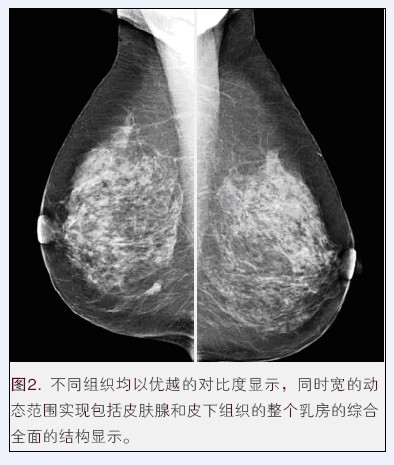

乳腺X射線機作為如今各大醫(yī)院及機構主要的放射科設備之一,為女性健康提供了先進的檢測平臺,是如今醫(yī)學領域檢測患者乳腺癌變等狀況的必備醫(yī)療器械。然而,隨著醫(yī)學事業(yè)的快速發(fā)展,醫(yī)療器械行業(yè)發(fā)生了翻天覆地的變化,生產乳腺X射線機的醫(yī)療器械公司也越來越多,那么到底乳腺X射線機哪個牌子好呢?

這就不得不提到國內具有較高知名度的普朗醫(yī)療。普朗BTX-9800系列乳腺機是如今女性乳腺癌早期診斷的金標準,不僅可以發(fā)現(xiàn)0.1毫米的鈣化點,還能夠有效提示癌前病變,是乳腺炎癥、乳腺增生、乳腺纖維瘤等疾病監(jiān)測的必備設備。更多資料,點擊產品圖下方的紅色產品名稱進入指定頁面

(普朗醫(yī)療品牌——BTX-9800高頻鉬靶乳腺X光機(乳腺X射線機))